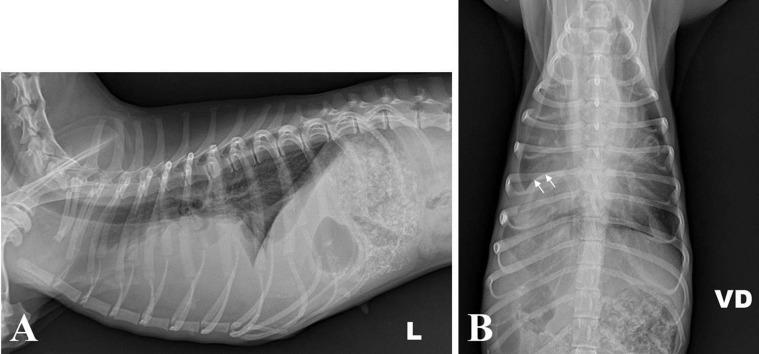

A four-year-old dachshund presented with a two-week history of pyrexia, depression, and cough. Four months earlier, the owner observed the dog swallow a whole popsicle stick, but the animal showed no clinical signs at that time. Radiography, ultrasonography, and computed tomography confirmed an intrathoracic linear foreign body and pleural effusion in the right thorax. The pleural fluid was bloody and purulent, and contained inflammatory cells and Escherichia coli. The dog was diagnosed with pyothorax induced by a foreign body, and was treated successfully by surgical removal of the foreign body, partial lung lobectomy, thoracic lavage, and antibiotics. The foreign body was identified as a popsicle stick that the dog had eaten.

一只四岁的腊肠犬出现发热、抑郁和咳嗽症状两周。四个月前,主人观察到这只狗吞下了一整根冰棒棍,但当时该动物没有表现出临床症状。X线摄影、超声检查和计算机断层扫描证实胸腔内有线性异物,右侧胸腔有胸腔积液。胸腔积液呈血性和脓性,含有炎性细胞和大肠杆菌。这只狗被诊断为异物引起的脓胸,并通过手术取出异物、部分肺叶切除、胸腔灌洗和使用抗生素成功治愈。异物被确定为这只狗吞食的冰棒棍。